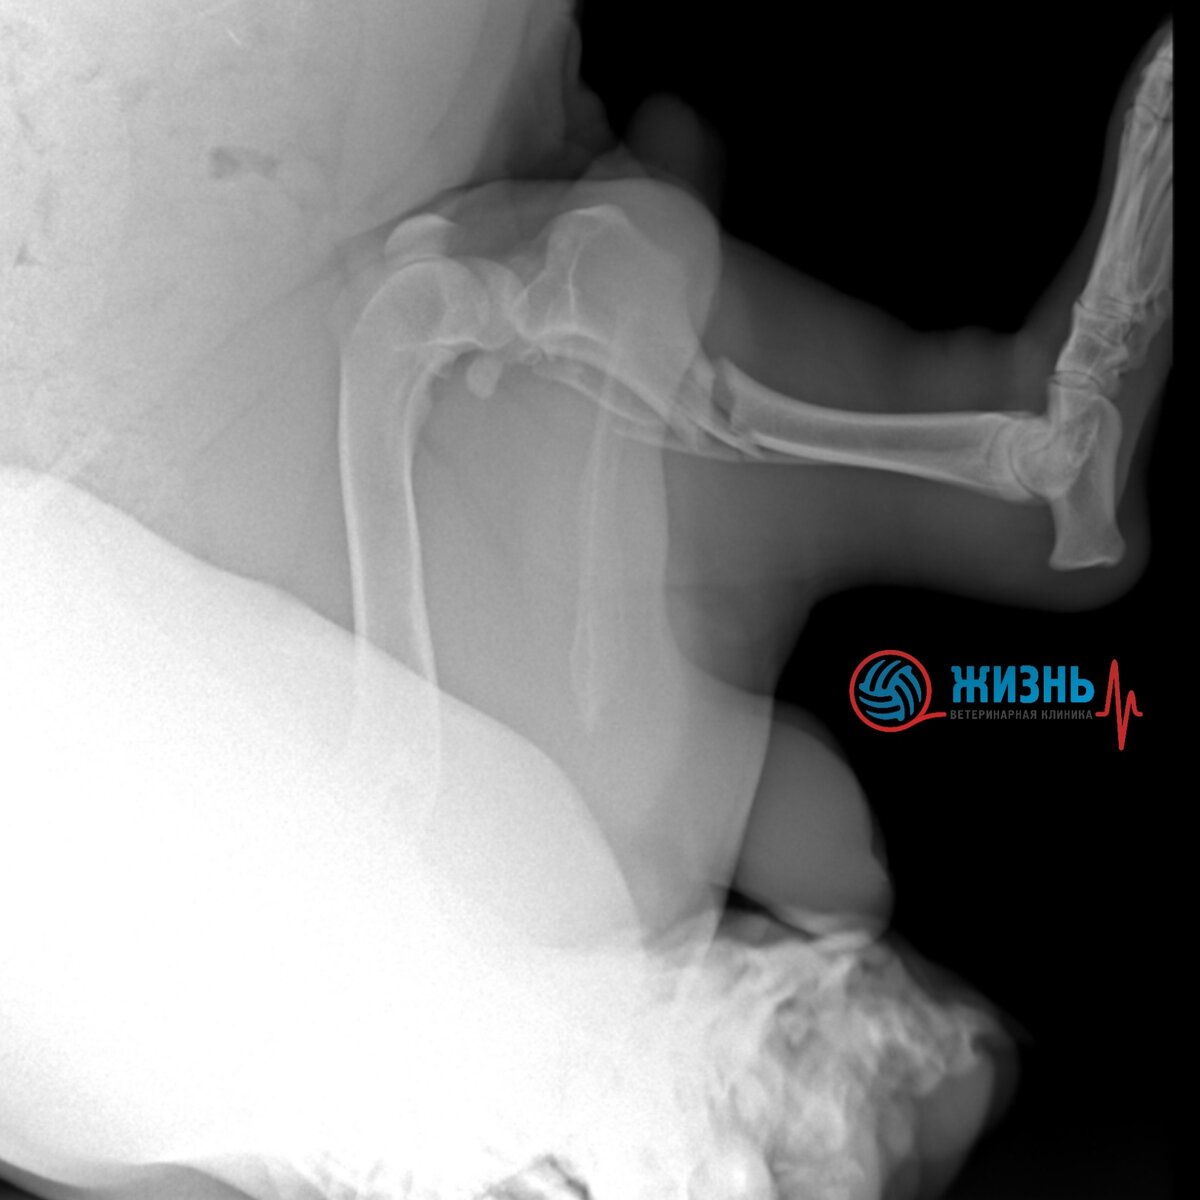

Рентген перелома лапы у собаки.

Оставался вопрос с лапкой. Шане сделали рентген тазовой конечности, на снимке врачи увидели перелом большеберцовой кости. Было принято решение проводить операцию, собирать перелом. Шане провели остеосинтез большеберцовой кости пластиной с угловой стабильностью. Операция прошла в штатном режиме. Шаня уже восстанавливается, когда ходит медленно, уже уверенно опирается на лапку.